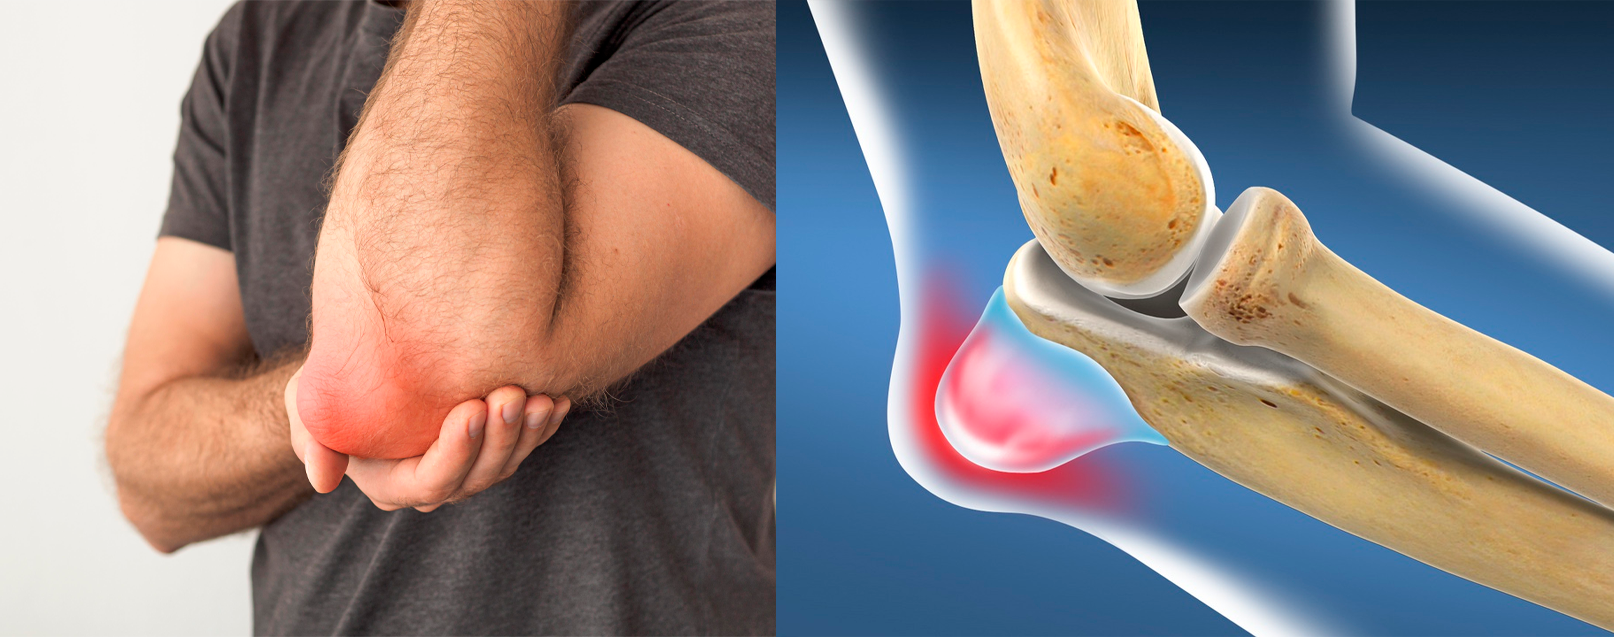

Bursite Olecraniana

Bursite Olecraniana

A bursite olecraniana é a inflamação da bursa localizada na ponta do cotovelo. Pode ser causada por traumas, esforço repetitivo ou até infecções. Os sintomas incluem dor, calor local e inchaço evidente. Na maioria dos casos, o tratamento é conservador, mas pode exigir drenagem ou cirurgia quando há complicações.